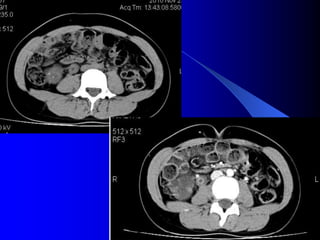

4.2. U bãøtháûn, niãûu quaín vaì baìng quang * Laì loaûi u biãøu mä âæåìng dáùn niãûu aïc tênh, chiãúm 6-10% caïc u tháûn aïc tênh. Caïc yãúu täú nguy cå chênh laì soíi tiãút niãûu, nhiãùm truìng, nghiãûn thuäúc laï, duìng quaï nhiãöu thuäúc phenacetin. Hay gàûp > 50tuäøi, nam = 2næî. * U laình tênh: polyp, hay gàûp âäü tuäøi 20-40. * U aïc tênh: chuí yãúu Carcinome tãú baìo chuyãøn tiãúp (85%), ngoaìi ra Carcinome tãú baìo vaíy (15%). Di càn ung thæ âãún âæåìng dáùn niãûu hiãúm gàûp. * U âæåìng dáùn niãûu hay gàûp theo thæï tæû åí baìng quang, bãø tháûn, niãûu quaín.

- NÂTM + Âäúivåïi thãø thám nhiãùm coï hçnh aính heûp, båì khäng âãöu, thæåìng gáy æï næåïc. + Âäúi våïi thãø suìi, coï hçnh khuyãút saïng trong âæåìng dáùn niãûu, båì coï thãø khäng âãöu, coï thãø gáy æï næåïc âæåìng dáùn niãûu phêa trãn. Cáön phán biãût våïi cuûc maïu âäng vaì soíi KCQ. ٠Soíi vaì maïu cuûc di chuyãøn vë trê, coï viãön caín quang bao quanh. ٠Maïu cuûc thay âäùi hçnh daûng theo thåìi gian. ٠U âæåìng dáùn niãûu (bãø tháûn, niãûu quaín, baìng quang) coï hçnh aính chán baïm vaìo thaình, nåi khäng coï viãön TCQ bao quanh u.

- Càõt låïpvi tênh Hçnh aính u giaím tè troüng so våïi nhu mä tháûn vaì tàng tè troüng sau khi tiãm TCQ. CLVT coï thãø tháúy: Maïu cuûc vaì soíi trong âæåìng dáùn niãûu coï tè troüng cao hån u (20-30UH). Soíi 100 - >1000UH tuìy thaình pháön cáúu taûo vaì maïu cuûc 50-70UH. U bãø tháûn coï thãø thám nháûp nhu mä laìm thay âäøi båì tháûn, coï thãø laìm heûp tàõc âæåìng baìi xuáút, giaîn ÂBT, coï thãø phaït hiãûn âæåüc trãn NÂTM. CLVT phaït hiãûn u bãø tháûn xám nháûp nhu mä tháûn dãù hån, âäöng thåìi phán biãût âæåüc våïi u nhu mä tháûn xám láún bãø tháûn.